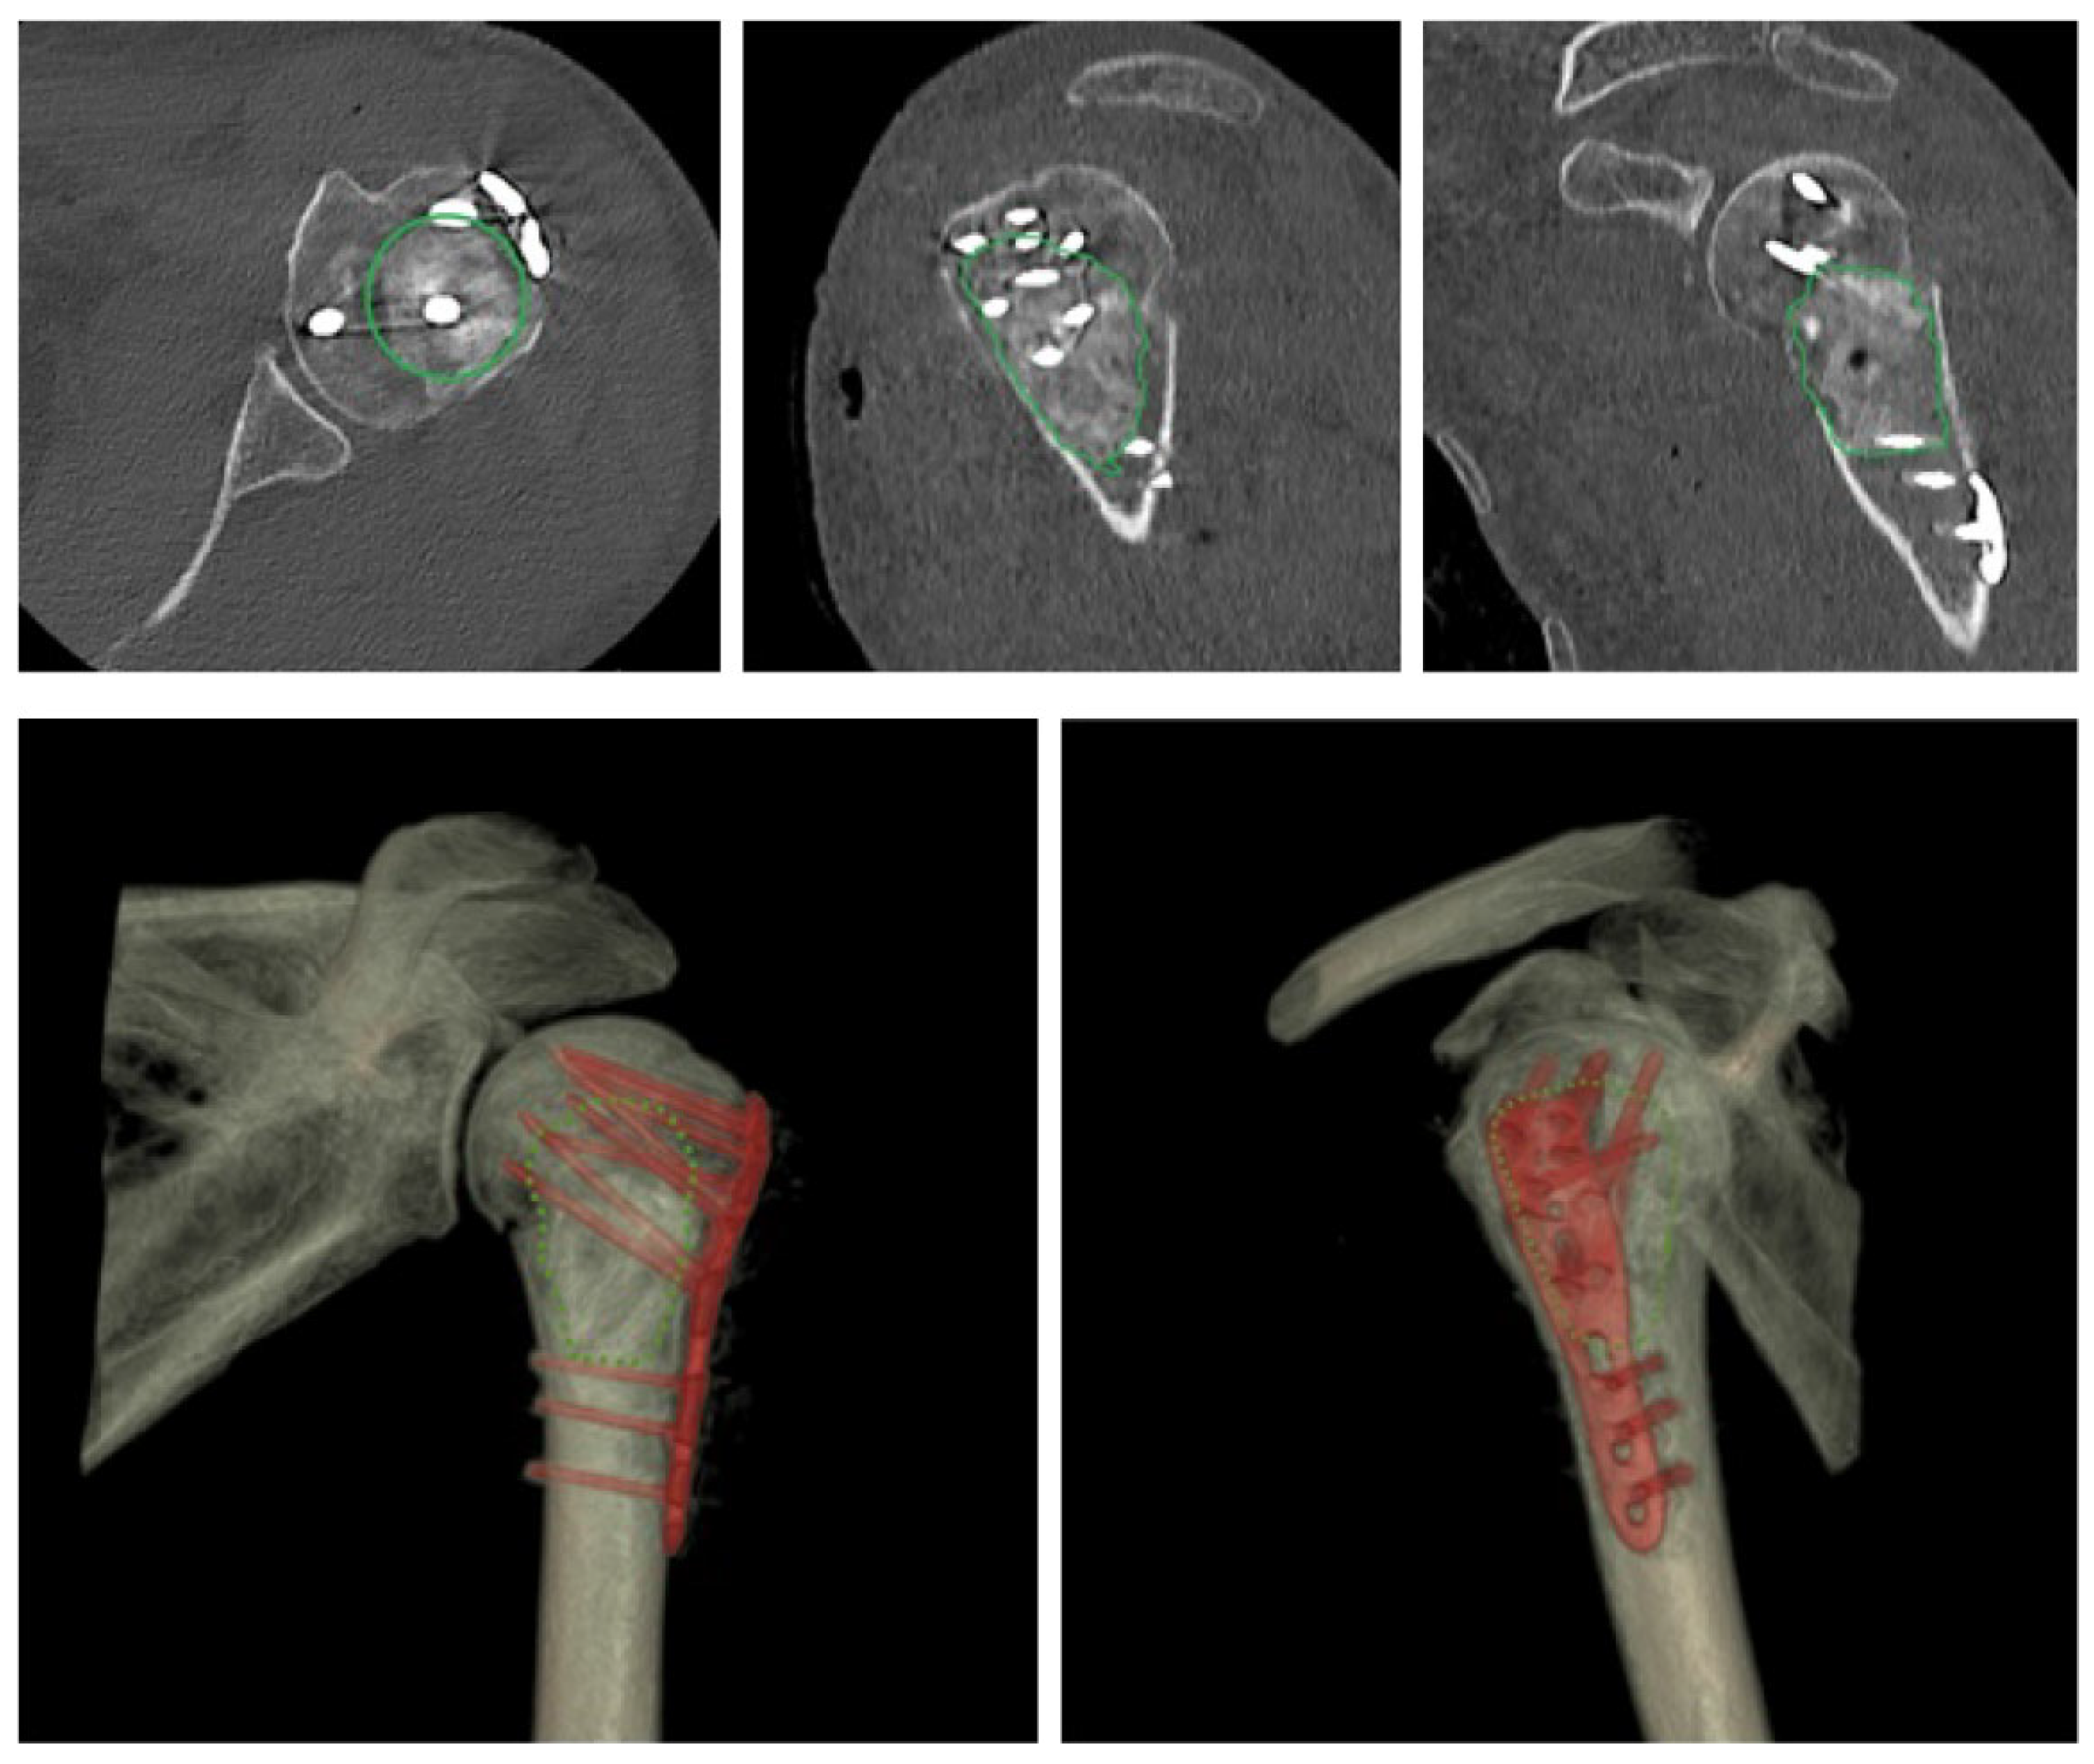

2. Materials and Methods